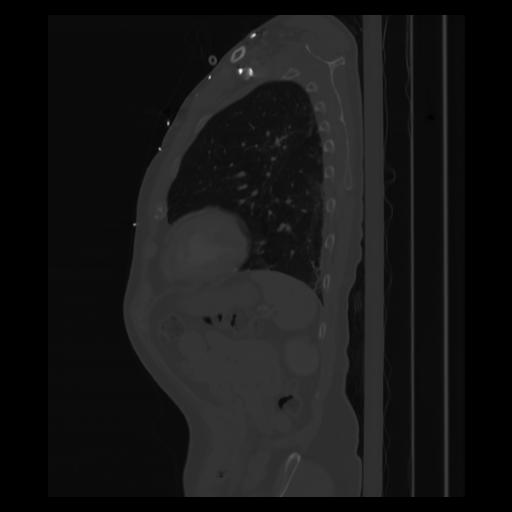

30 CUERPO,CE,Sagittal,3.000,CUERPO,Sagittal,